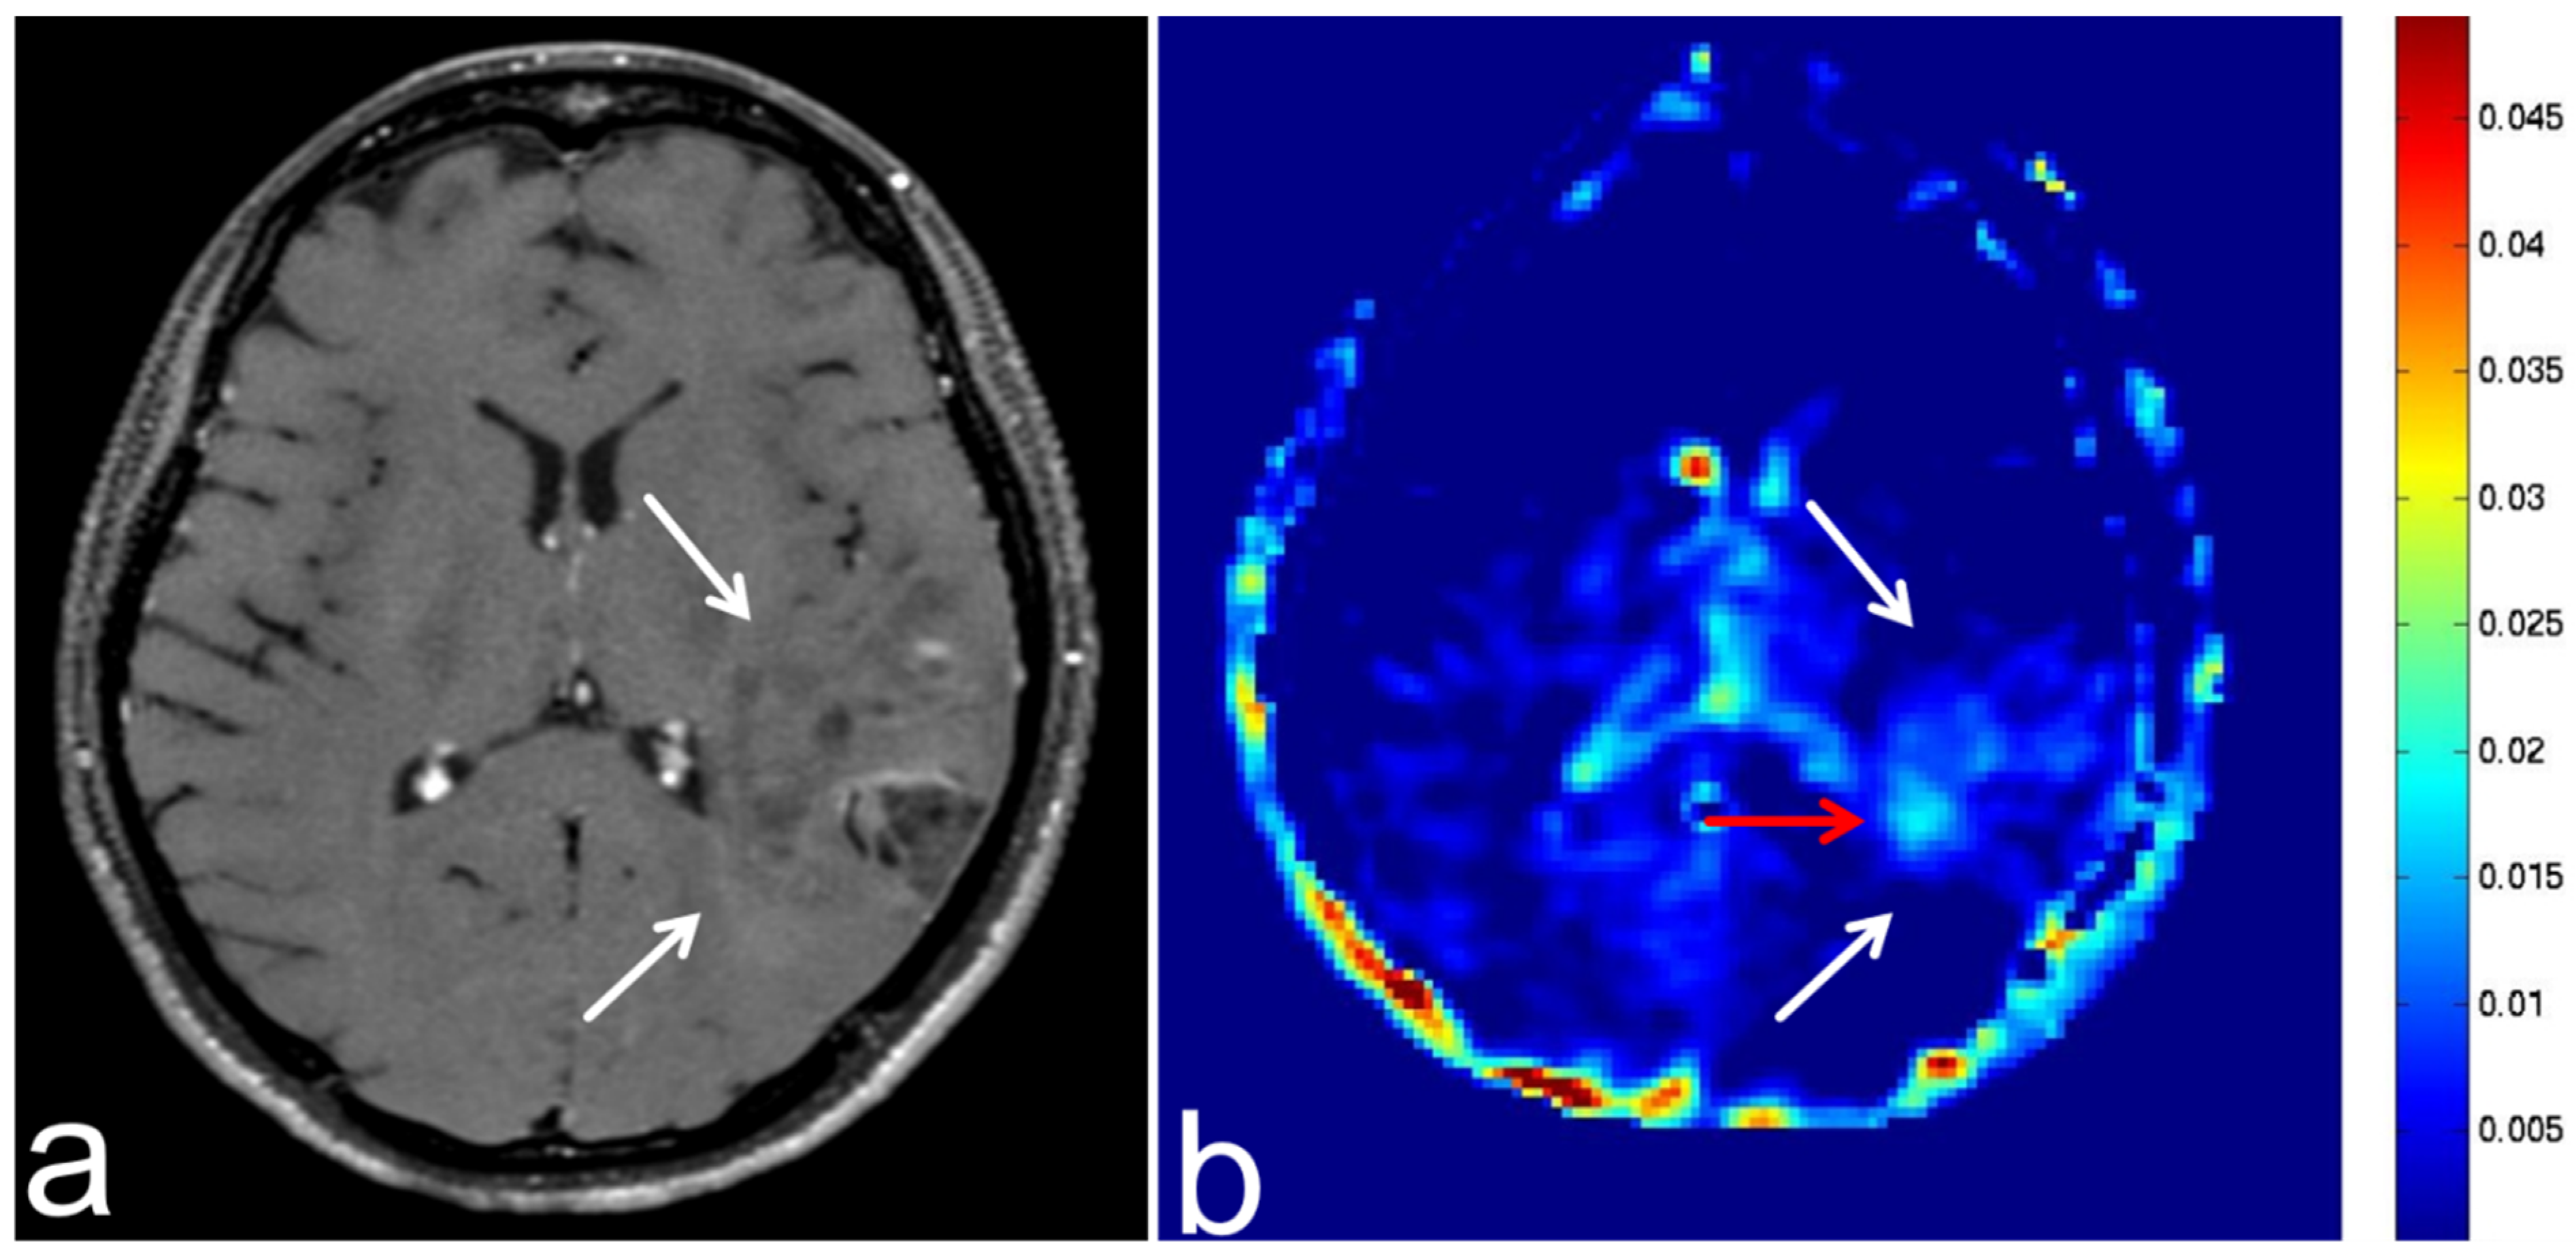

5.3. Glioblastoma